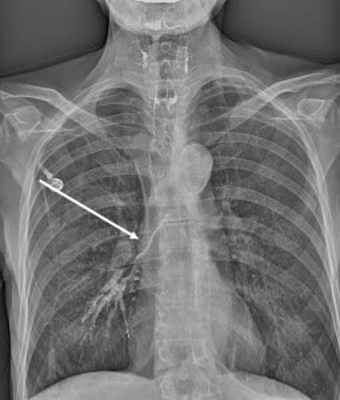

- Обязательным является проведение рентгенографии и рентгеноскопии пищевода с водорастворимым контрастным веществом (барий использовать не рекомендуется, рисунок 1, 2).

Рисунок 1. Пищеводно-респираторный свищ при рентгенографии/рентгеноскопии пищевода

Рисунок 2. Остатки бария сульфата в бронхах у пациентки с пищеводно-бронхиальными свищами